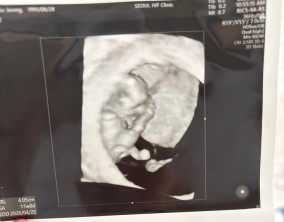

심장소리 이후, 함께 웃게 된 임밍아웃